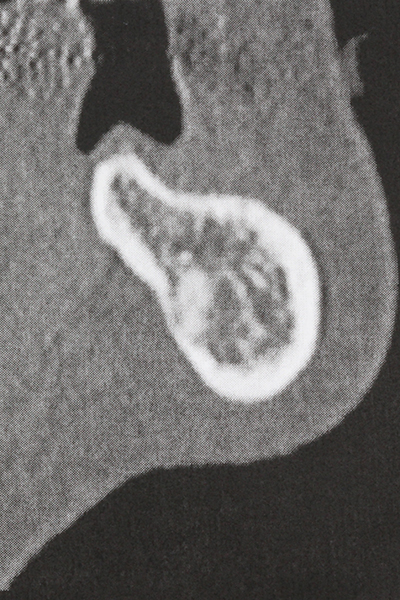

Weitere Einsatzgebiete ergeben sich in der Kieferhöhlenchirurgie: Hier können nach konzentrischer Präparation eines in der Regel trapezförmigen Knochendeckels der fazialen Kieferhöhlenwand Pathologien und Fremdkörper aus der Kieferhöhle entfernt werden. Der Knochendeckel wird nach Abschluss des intra-antralen Operationsanteils reponiert und durch Verkeilen oder adaptierende Nähte gegen Dislokation gesichert.